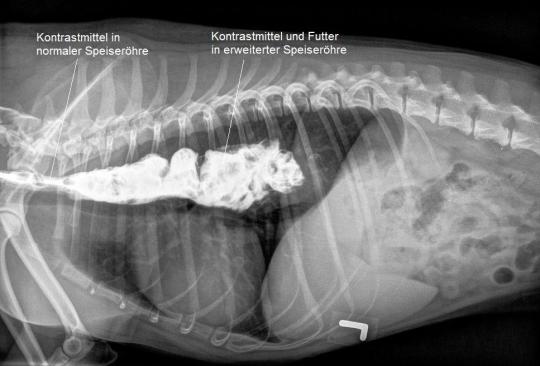

Das Bruströngen ist verdächtig für eine Erweiterung der Speiseröhre in diesem Bereich. Zur weiteren Abklärung erhält Jago nun Futter, welches mit einem Röntgenkontrastmittel vermischt ist. In einer weiteren Röntgenaufnahme wird dann dokumentiert, dass das geschluckte Futter nicht ordnungsgemäss im Magen gelandet ist, sondern in der stark erweiterten Speiseröhre in der Brusthöhle liegen geblieben ist - der Hund leidet unter einem Megaösophagus.

In der Folge werden noch drei Labortests durchgeführt, um zu eruieren, ob die Speiseröhrenerweiterung einen dokumentierbaren Auslöser hat. Alle 3 Tests verlaufen jedoch negativ, weshalb die Diagnose eines "idiopathischen Megaösophagus" (idiopathisch = aus sich selbst entstehend) gestellt wird.